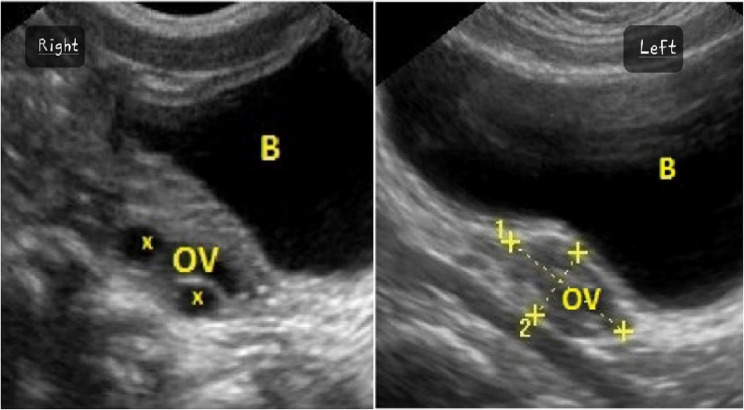

先天性甲状腺功能减退症(CH)是一种常见的疾病,如果不及时诊断和治疗,可导致婴儿显著的神经发育问题。Van Wyk和Grumbach综合征(VWGS)以甲状腺功能减退、性早熟和卵巢肿块为特征,由于诊断资源有限,在中低收入国家(LMICs)经常被误诊。这个病例强调了系统性的挑战,包括延迟诊断和不必要的手术转诊。我们报告一个8岁的女孩被诊断为Van Wyk-Grumbach综合征,其特征是严重的甲状腺功能减退,同性性早熟和卵巢过度刺激。她的症状包括阴道出血、腹胀和明显的肥胖并发育不良。检查显示严重甲状腺功能减退(TSH: 96 mU/L)和双侧卵巢囊肿增大。在开始左旋甲状腺素治疗后,患者表现出显著的临床改善,包括腹部肿胀减轻和甲状腺功能正常化。本病例强调了在儿童卵巢肿块鉴别诊断中考虑甲状腺功能减退的重要性,特别是在缺乏新生儿筛查方案的地区,以防止不必要的手术干预并确保对病情的适当管理。

Congenital hypothyroidism (CH) is a prevalent condition that can lead to significant neurodevelopmental issues in infants if not diagnosed and treated promptly. Van Wyk and Grumbach Syndrome (VWGS), characterized by hypothyroidism, precocious puberty, and ovarian masses, is often misdiagnosed in low- and middle-income countries (LMICs) due to limited diagnostic resources. This case highlights systemic challenges, including delayed diagnosis and unnecessary surgical referrals.We present an 8-year-old girl diagnosed with Van Wyk-Grumbach syndrome, characterized by severe hypothyroidism, isosexual precocious puberty, and ovarian hyperstimulation. She exhibited symptoms including vaginal bleeding, abdominal distention, and marked obesity with stunted growth. Investigations revealed severe hypothyroidism (TSH: 96 mU/L) and enlarged bilateral ovarian cysts. After initiating levothyroxine therapy, the patient demonstrated remarkable clinical improvement, including reduced abdominal swelling and normalizing thyroid function. This case underscores the importance of considering hypothyroidism in differential diagnoses of ovarian masses in children, especially in regions lacking newborn screening protocols, to prevent unnecessary surgical interventions and ensure appropriate management of the condition.